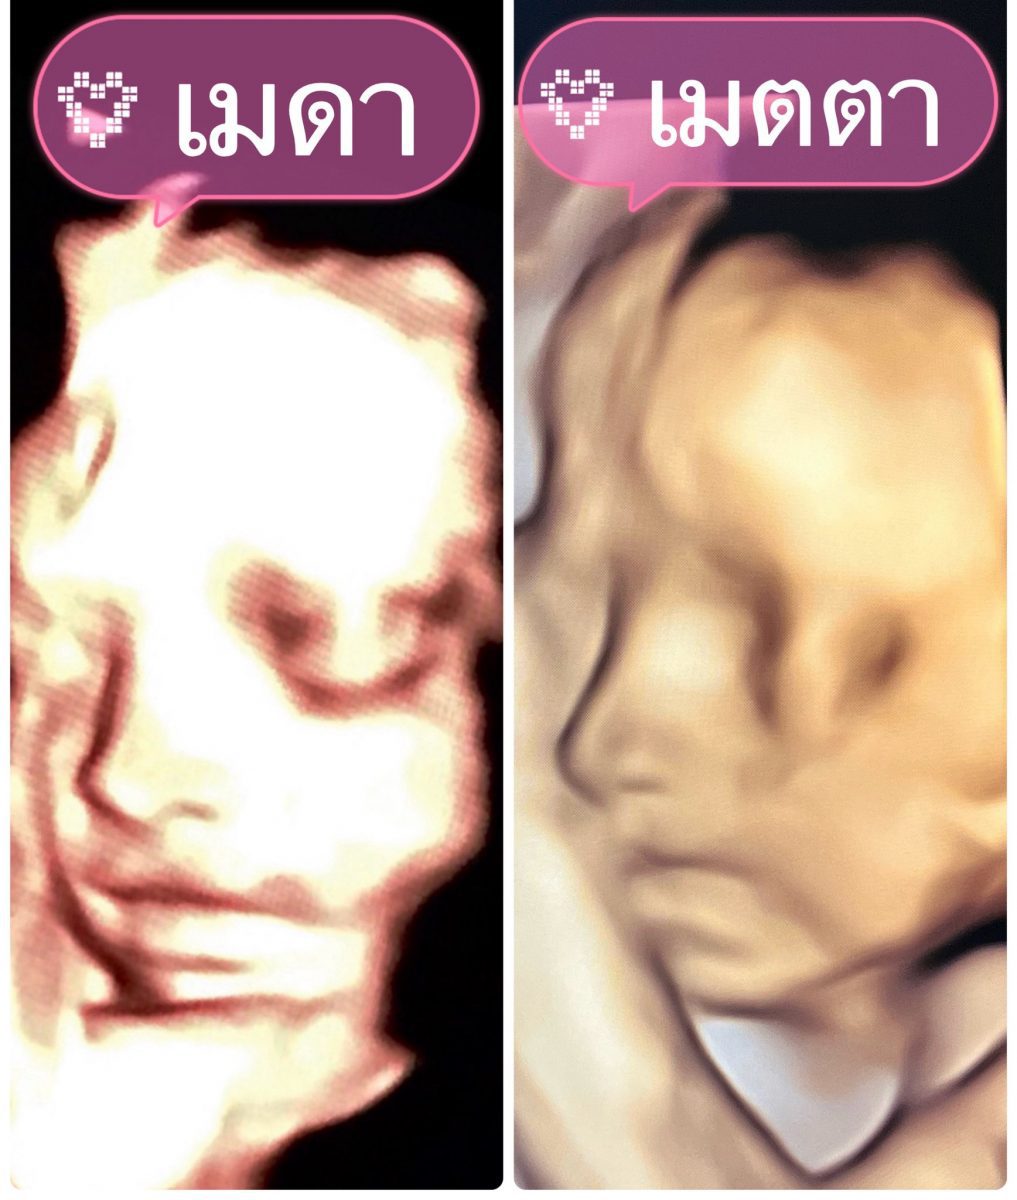

ด้าน “เจมส์ เรืองศักดิ์” ทำหน้าที่ดูแลภรรยาและลูกน้อยในครรภ์ไม่ห่าง พร้อมโพสต์ข้อความผ่านโซเซียลมีเดียว่าอบ “องครักษ์พิทักษ์คนท้อง” และ “ช่วงเวลาอันแสนพิเศษของครอบครัวเรา” ควบคู่กับภาพอัลตราซาวด์ที่เผยให้เห็นความละม้ายคล้ายคลึงของลูกสาวทั้งสองคน “น้องเมดา” และ “น้องมีเมตตา” สร้างรอยยิ้มและความประทับใจให้กับผู้ติดตามจำนวนมาก

นอกจากนี้ ครูก้อย ยังอัปเดตภาพอัลตราซาวด์ “น้องมีเมตตา” อายุครรภ์ 26 สัปดาห์ แบบอารมณ์ดีว่า ลูกสาวชอบเอามือบังหน้า ทำให้เห็นไม่ชัดสักที แต่แอบเห็นมุมข้างหน้าเรียว ๆ น้ำหนักตอนนี้กว่า 800 กรัม อยู่ในเกณฑ์มาตรฐาน ขณะที่น้ำหนักคุณแม่อยู่ที่ 69 กิโลกรัม และยังเพิ่มตามเกณฑ์เหมาะสม